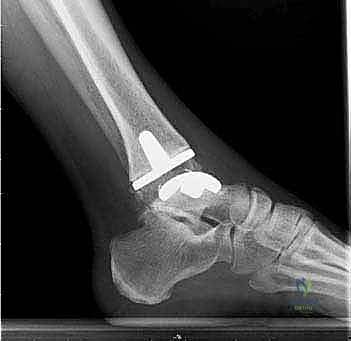

يتكون مفصل الكاحل الصناعي الحديث عادة من ثلاثة أجزاء:

* قطعة معدنية علوية: تُثبت في عظمة الظنبوب (الساق).

* قطعة معدنية سفلية: تُثبت في عظمة الكاحل.

* قطعة بلاستيكية (بولي إيثيلين عالي الكثافة): توضع بين القطعتين المعدنيتين لتنزلق بسلاسة وتمتص الصدمات، محاكيةً وظيفة الغضروف الطبيعي.

يتم تثبيت هذه الأجزاء بإحكام (إما عن طريق الضغط المباشر لتشجيع نمو العظم حولها، أو باستخدام أسمنت طبي خاص).